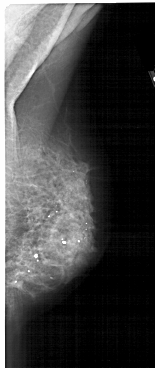

A_1505_1.LEFT_MLO

LEFT_MLO LINES 4966 PIXELS_PER_LINE 2011 BITS_PER_PIXEL 12 RESOLUTION 43.5 OVERLAY

FILE: A_1505_1.LEFT_MLO.OVERLAY

TOTAL_ABNORMALITIES 1

ABNORMALITY 1

LESION_TYPE CALCIFICATION TYPE PLEOMORPHIC DISTRIBUTION SEGMENTAL

LESION_TYPE MASS SHAPE ARCHITECTURAL_DISTORTION MARGINS ILL_DEFINED

ASSESSMENT 4

SUBTLETY 3

PATHOLOGY MALIGNANT

TOTAL_OUTLINES 1